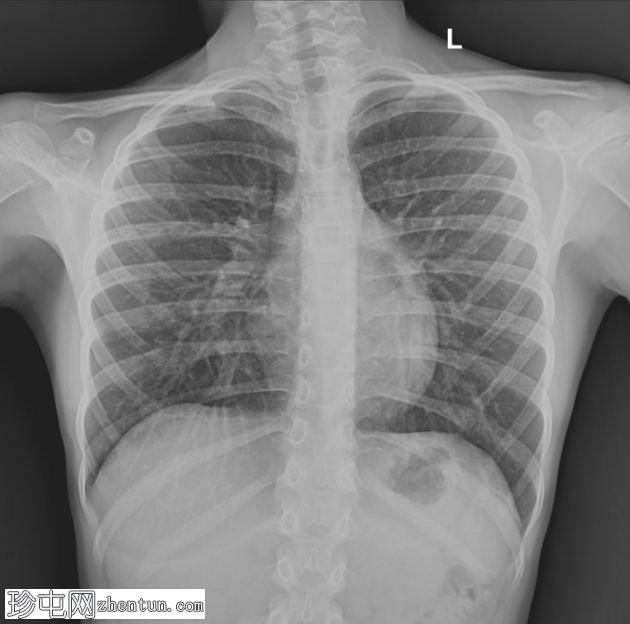

X线片

双

肺

野清晰。肺门外观正常。膈肌穹隆和肋膈角正常。

心脏

轮廓向左移位并呈细长状。右心缘部分模糊。降主动脉与胸主动脉交界处模糊。可见肋骨方向异常,后肋相对水平,前肋呈垂直方向。

漏斗胸会导致胸部X线片上出现继发性心纵隔轮廓改变

心脏向左移位且右心缘模糊是其特征性表现

肋骨方向异常有助于诊断

CT主要用于定量分析和手术计划